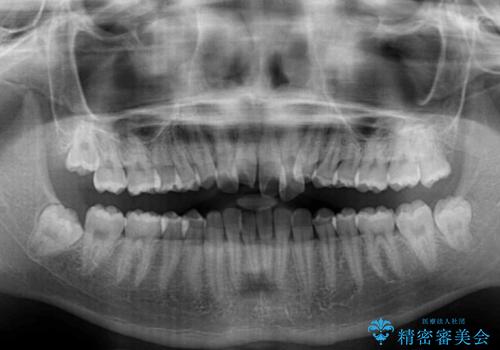

- 前歯のクロスバイトを気にして来院された患者様です。

歯がすり減って不揃いの形態となっていますが、まずは矯正治療によりクロスバイトを改善することとしました。